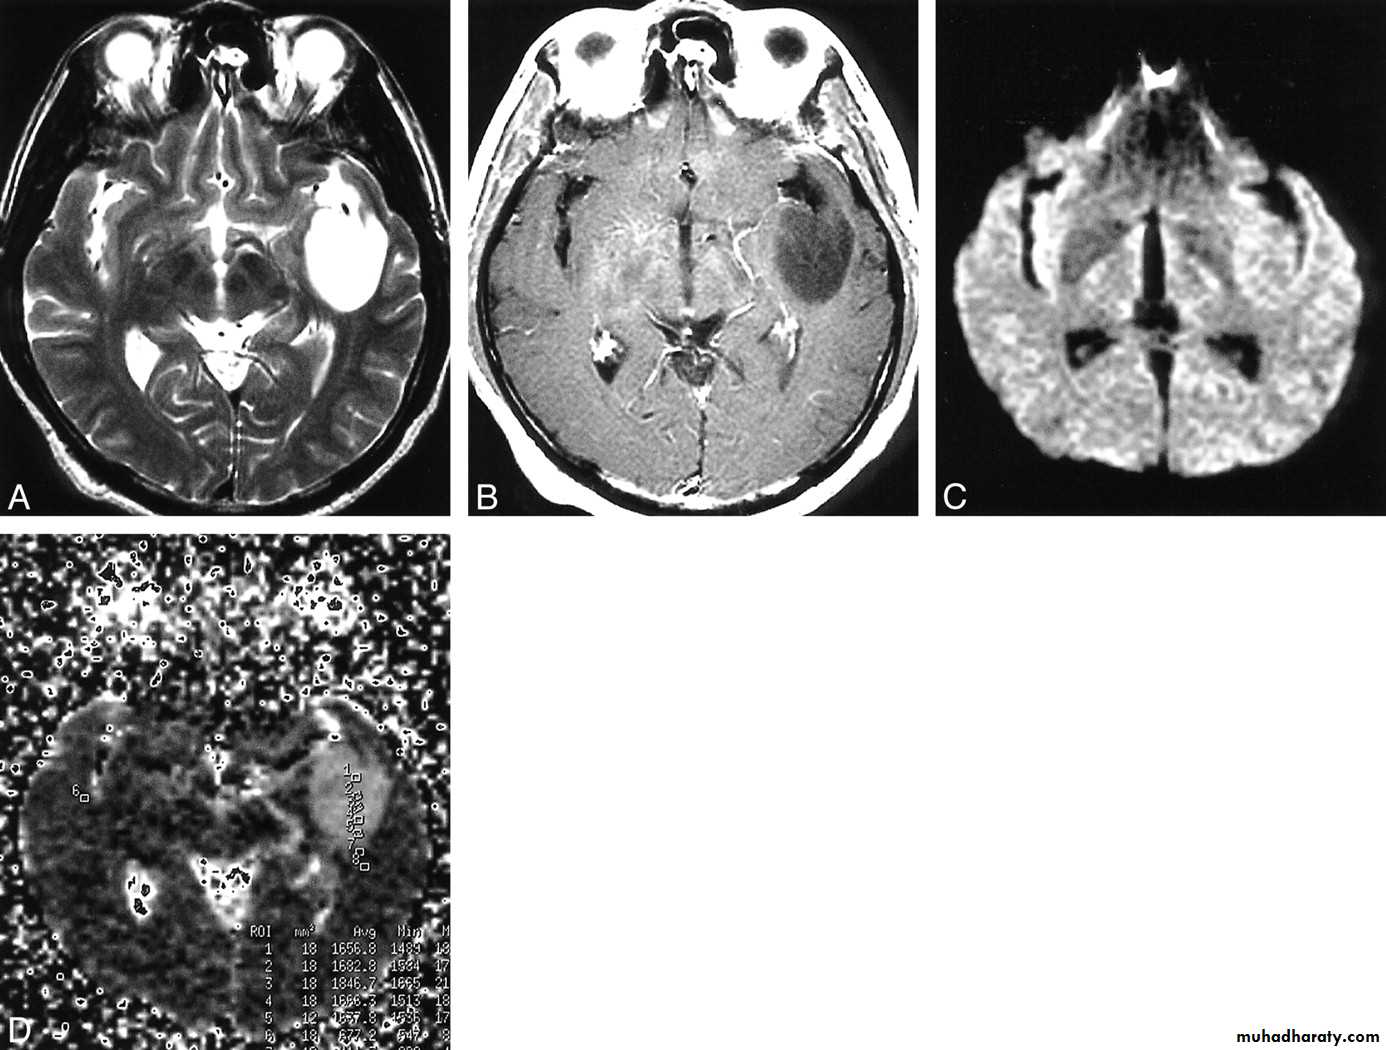

These are the most common primary tumors they arise form the glial cells which are part of the supportive tissue of the brain

There are many types of glioma with different degrees of malignancy:

Astrocytomas:have 4 grades I -> IV. These are the most common gliomas, there are 4 grade of astrocytoma depending on the degree of malignancy, it can affect any age , usually yellow - whitish in color affecting both cerebrum and cerebellum , it can affect ages from 2 months ~ 95 years.

Glioblastoma multiformis:

The most malignant brain tumor, rapidly growing , red in color, highly vascular mainly affecting the cerebrum , some pathologists classify it as astrocytoma grade IV.Medulloblastoma:

arise from the epidermal lining of the ventricular system, usually whitish in color & can lead to early hydrocephalusCT scan of all gliomas shows usually hyperdense lesion, irregular in shape, surrounded by edema & may be enhanced with or without cystic degeneration.

Note: all gliomas are dealt with by surgical intervention ,by excision of the tumor followed by radiotherapy , but prognosis is not very good & fluctuates from 5 years survival of less than 5% in Glioblastoma multiformis to up to 100% 5 years survival in Oligodendroglioma treated by surgery & successive radiotherapy.